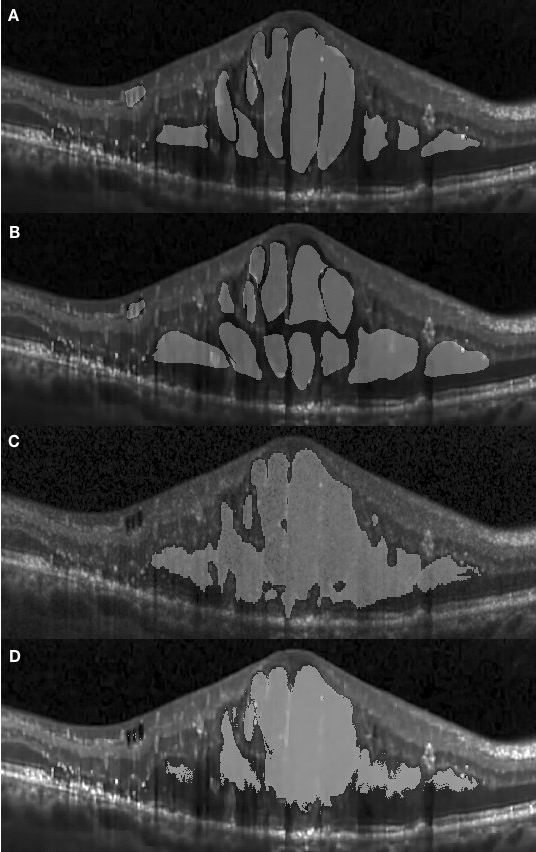

Figure 4.2 (A) shows a concrete edema embedded within retinal layers on the right-hand side of the fovea region. The distinctive features of this edema are not visually recognizable in this OCT image due to low contrast within the retinal layers. However the presence of the edema causes a deformation of the retinal layers on the right-hand side, with a corresponding change of the layer interval, making them noticeably thicker than those on left-hand side. It is observed in Fig. 4.2 (D) that the segmented results obtained with our approach presents a high correspondence to the manually segmented results. However, it is worth noting that our approach has segmented several regions which had been represented separately under manual annotation as a single large one.